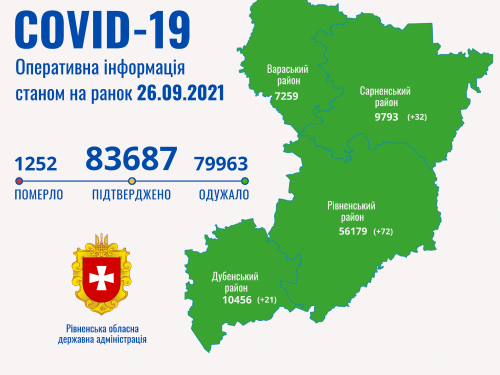

Пів тисячі - у важкому стані, 9 жителів Рівненщини померли за добу від коронавірусу